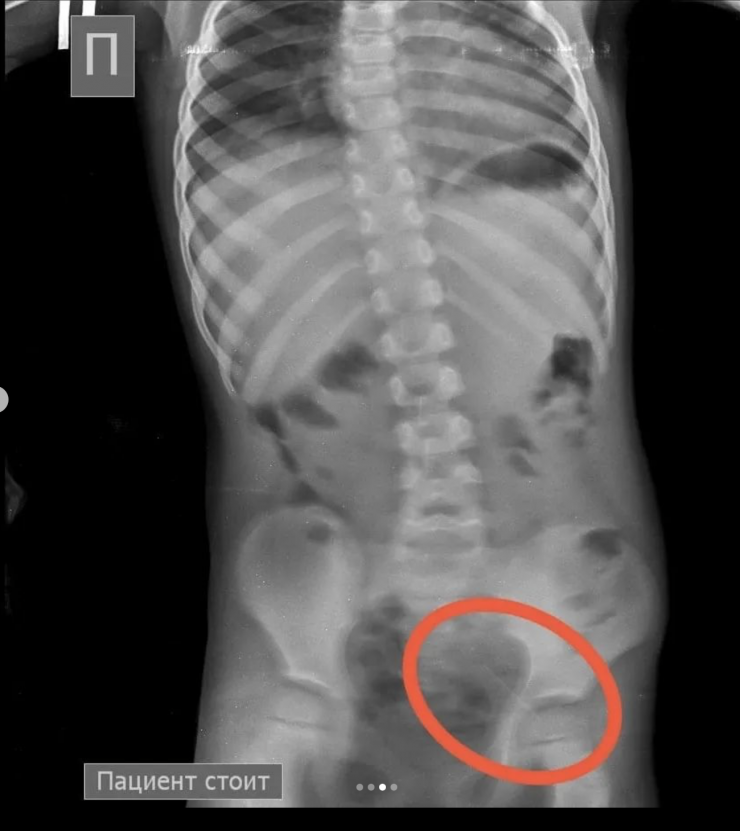

"На обзорной рентгенограмме брюшной полости был обнаружен бегунок и, предположительно, две швейные иглы в проекции желудка. При проведении процедуры ЭФГДС из желудка удалена одна игла, бегунок отсутствовал. Пациент был оставлен в хирургическом отделении Жамбылской областной многопрофильной детской больницы под наблюдением специалистов", - рассказали врачи детской больницы.

В результате бегунок со стулом вышел самостоятельно. В то же время другая игла не выходила.